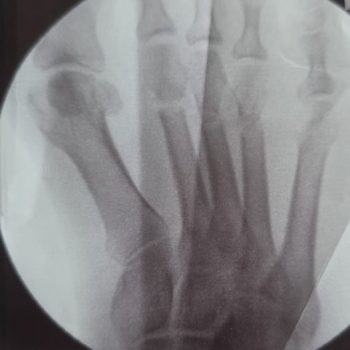

Es gibt verschiedene radiologische Methoden, den Sichelfuß am Röntgenbild zu quantifizieren. Sie alle messen im Prinzip dasselbe: den Winkel zwischen Vorfuß und Rückfuß auf der Belastungsaufnahme im Stehen — also genau dort, wo die Fehlstellung klinisch relevant wird.

Leichte und mittelschwere Formen sind auch für den erfahrenen Untersucher in der klinischen Untersuchung kaum sicher zu erkennen — zu gut haben sich die meisten Betroffenen über Jahre mit ihrer Fehlstellung arrangiert. Erst die belastete Röntgenaufnahme im Stehen oder das DVT macht das Ausmaß der Fehlstellung zuverlässig sichtbar.

In unserer Praxis nutzen wir bevorzugt den Engel-Winkel — eine Methode, die 1983 von Engel, Erlick und Krems beschrieben wurde und sich seither in der klinischen Praxis bewährt hat [Engel et al., J Am Podiatry Assoc, 1983]. Der Engel-Winkel misst den Winkel zwischen der Längsachse des zweiten Mittelfußknochens und der Längsachse des zweiten Keilbeins auf der belasteten Röntgenaufnahme. Er ist schnell zu bestimmen, gut reproduzierbar und für die klinische Entscheidungsfindung ausreichend genau.